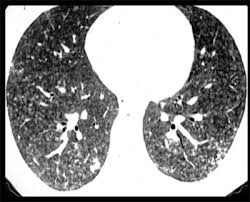

Τα ακτινολογικά ευρήματα επί ΠΥ είνμαι παρόμοια, ανεξάρτητα από τον αιτιολογικό παράγοντα που τα προκάλεσε και μπορούν να διακριθούν σε τρεις κατηγορίες: οξέα, υποξέα και χρόνια. Η αξονική τομογραφία υψηλής αναλύσεως εμφανίζει εικόνα θαμβής υάλου στις οξείες μορφές, εστίες παγιδεύσεως αέρα με διάχυτα μικροοζίδια, στις υποξείες μορφές, και εκτεταμένη ίνωση με εικόνα μελιτοκηρύθρας και παγίδευση αέρος, στις χρόνιες. Η απλή ακτινογραφία περιγράφεται αλλού. Στις συμπληρωματικές διαγνωστικές εξετάσεις περιλαμβάνονται δοκιμασίες προκλήσεως, λήψη BAL λειτουργικές δοκιμασίες αναπνοής, και βιοψία ανοικτού πνεύμονος, που θα βοηθήσουν στην τεκμηρίωση της διαγνώσεως και την ταυτοποίηση του αιτιολογικού παράγοντος.

υποξεία μορφή πνευμονίας εξ υπερευαισθησίας. [α] φυσιολογική ακτινογραφία θώρακος, παρ΄όλο ότι η HRCT εμφανίζει εικόνα θαμβής υάλου στα άνω πνευμονικά πεδία και τις υπολεύριες περιοχές. οζίδια

υποξεία μορφή πνευμονίας εξ υπερευαισθησίας. εμβαλωματικές περιχοές θαμβής υάλου, αμφοτερόπλευρα. παγίδευαη αέρος στο εκπνευστικό (Β) και εικόνα μωσαϊκού υποξεία μορφή πνευμονίας εξ υπερευαισθησίας. μερικά λοβίδια (βέλη) φαίνονται άθκτα. Το εύρημα αυτό είναι ενδεικτικό παγιδεύσεως αέρος και εικόνας μωσαϊκού υποξεία μορφή πνευμονίας εξ υπερευαισθησίας. Αμφοτερόπλευρες εικόνες θαμβής υάλου. χρόνια μορφή πνευμονίας εξ υπερευαισθησίας. ίνωση, εικόνα μελιττοκηρύθρας, εξ έλξεως βρογχεκτασίες, και ανώμαλες δικτυώδεις σκιάσεις. χρόνια πνευμονία εξ υπερευαισθησίας, με ευρήματα υποξεία επιθέσεως. περιοχές θαμβής υάλου κια ήπια ίνωση. χρόνια μορφή πνευμολνίας εξ υπερευαισθησίας. Στους μεν άνω λοβούς (Α) αναγνώριζεται πάχυνση μεσολβιδιίων διαφραγματίων και εξ έλεξεως βρογχιολεκτασίες (βέλη), ενώ στις βάσεις (Β), ίνωση με εικόνα μελιττοκηρύθρας.

απεικονιστικές εξετάσεις. H ακτινογραφία θώρακος μπορεί να είναι φυσιολογική, ιδίως μεταξύ των παροξύνσεων ή μπορεί να εμφανίζει διάχυτες σκιάσεις κατά τη διάρκεια των υφέσεων, αλλά η απλή ακτινογραφία θώρακος στερείται ειδικότητας ή ευαισθησίας, καθώς παθολογικά ευρήαμτα διπασιτώνονται σε <50% των περιπτώσεων. . Η αξονική τομογραφία περιγράφεται αλλού (πίνακας 4). Η κατανομή των βλαβών μπορεί να είναι διάχυτη ή εμβαλωματική (κατά νησίδες) και είναι περισσότερο ευκρινείς στος παραπυλαίες και βασικές περιοχές, Μικρές κυστοειδείς βλάβες, με λεπτά τοιχώματα που περιέχουν αέρα, έχουν επισημανθεί σε μικρό αριθμό ασθενών με υποξεία ΠΥ. Λοβιδιακού επίπεδου περιοχές μειωμένης ακτινολογικής πυκνότητας, και εκπευστική παγίδευση αέρος είναι συνήθεις (50-75%) και μέχρι 92% σε ασθενείς επί δυναμικών εισπνευστικών-εκπνευστικών ΗRCT. Η παγίδευση αέρος είναι, ιδίως, συχνή σε περιοχές με χαρακτήρες θαμβής υάλου και αποκαλύπτουν απόφραξη μικρών αεραγωγών (εικόνα μωσαϊκού). Γενικά, η ατινολογική απεικόνιση της ΠΥ μπορεί να συσχετιστεί με εκείνη επί σαρκοειδώσεως, ή της συνήθους διάμεσης πνευμονίτιδας (συνήθης διάμεση πνευμονία)UIP/IPF αλλά στις περιπτώσεις της ΠΥ οι βάβες είναι εμφαλωματικές και με τάση να συρρέουν στα μέσα πνευμονικά πεδία, ενώ αφήνουν σχετικά ανέπαφες της κορυφές (αν και όχι σε όλες τις περιπτώσεις) και τις βάσεις, ενώ οφείλουν να μην εδράζονται υποϋπεζωκοτικά.

χρόνια πνευμονία εξ υπερευαισθησίας. με ίνωση (πενικίλιουμ). Περιφερικές εικόνες μελιττοκηρύθρας, Η εικόνα, πλέον, είναι δυσδιάκριτη της πνευμονικής ινώσεως.